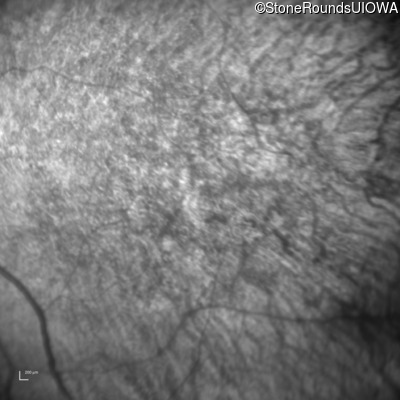

Age at visit: 41 years

This 41 year old man first came to medical attention at age 18 months when exotropia and amblyopia of his right eye were discovered. At age 11 vitreous strands and retinal vascular sheathing were seen. He has had poor night vision and constricted visual fields since his late teens. Later, at age 44 a traction retinal detachment was noted in his left eye and was treated with a scleral buckle.